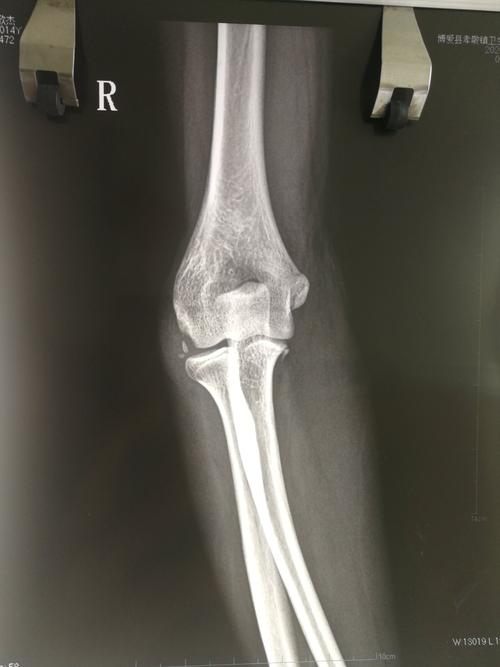

肘关节鹰嘴突出图片

肘关节鹰嘴突出图片,鹰嘴突的位置图片

14岁男孩,右肱骨外髁撕脱骨折,尺骨鹰嘴骨折.看需不需要手术?